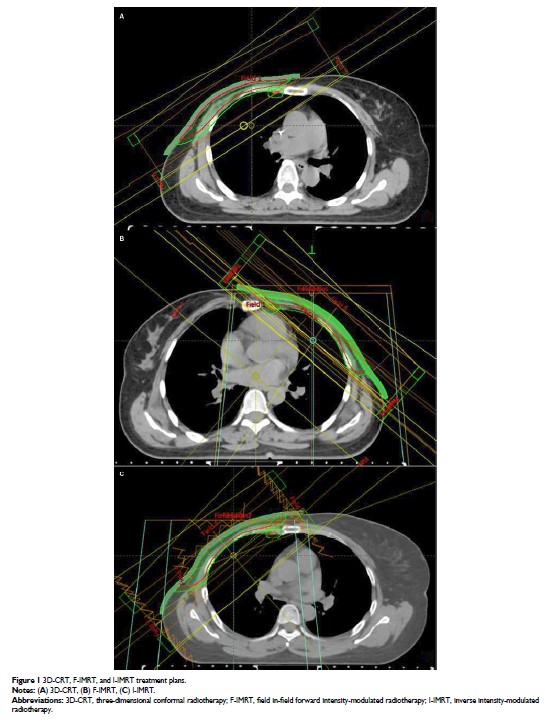

- 作者:Wei Wang, Yingjie Zhang, Min Xu, Qian Shao, Tao Sun, Ting Yu, Xijun Liu, Jianbin Li

- 期刊:Cancer Management and Research